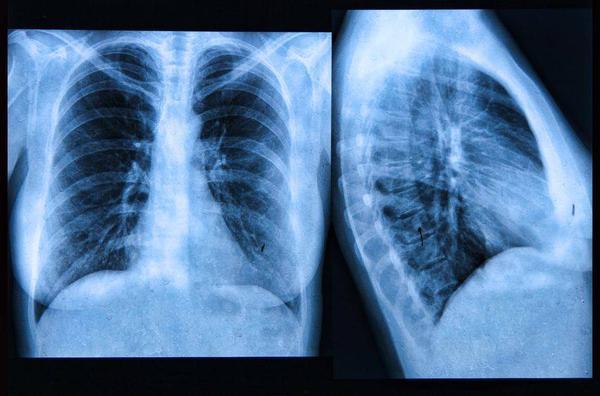

肺癌“偏爱”这4类人,若你符合,需注意加强养护肺脏,定期检查

肺癌算是一种赫赫有名的疾病 , 大多数人都知道患了肺癌之后 , 病情非常难以治愈 。

据统计 , 肺癌现目前已经成为了中国的第一癌 , 每年大概有71.8万人被确诊为肺癌 , 其中有超过50%的患者发现病情的时候已经是中晚期 , 能活过五年的患者不到两成 。

所以很多人都非常害怕患上肺癌 , 不过也有的人在平时中仍然不注意养成良好的生活习惯 , 导致肺癌的发病率增加 。